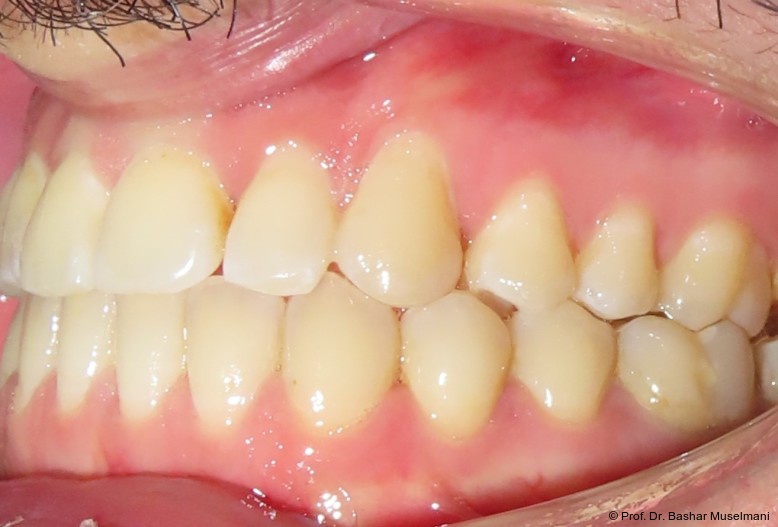

Abschlussbefund

Die Behandlung wurde mit 0.018 x 0.0275" TMA-Bögen abgeschlossen. Nach Entfernung der Multibracketapparatur zeigten sich:

• eine stabile Klasse I-Verzahnung

• ein normalisierter Overjet und Overbite

• deutliche Verbesserung der okklusalen Interdigitation

• ein ästhetisch harmonisiertes Profil

Die Behandlungsphase wird mit dem Einsetzen von TMA-Bögen im Ober- und Unterkiefer abgeschlossen (Abb. 10a–e). In den Abbildungen 11a bis c sind die extraoralen Aufnahmen nach Behandlungsabschluss und nach Entfernung der Brackets in beiden Kiefern dargestellt. Die Aufnahmen und die Kephalometrischen Analysen zeigen deutliche und rasche Veränderungen zwischen Behandlungsbeginn und -ende. Die Kephalometrischen Werten sind dabei von besonderer Bedeutung. Wie sich deutlich anhand des vergleiches der drei Behandlungsphase erkennen lässt.

Der Patient stellte sich erneut an der Universitätsklinik zur Beurteilung seines Zustands vor. Es wurde berichtet, dass keine chirurgische Behandlung der Dysgnathie mehr erforderlich ist.